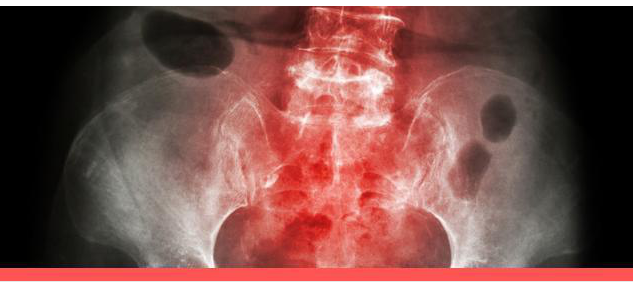

强直性脊柱炎是一种累及脊柱、骶髂关节和髋关节的慢性进展性疾病 ...

强直性脊柱炎是一种主要累及中轴骨骼的慢性炎症性疾病,其特点是 ...